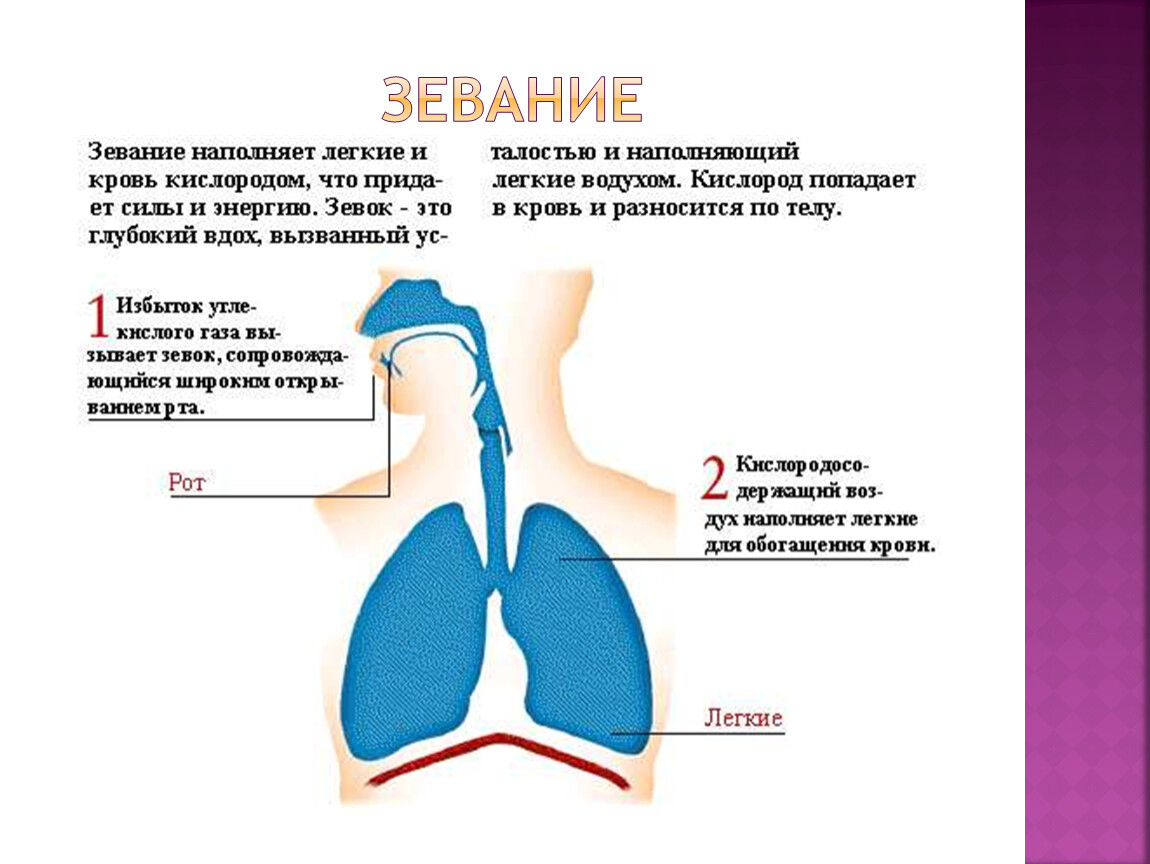

Эмоциональные фотографии: воздух легкий или тяжелый

Раздел: Точки зрения